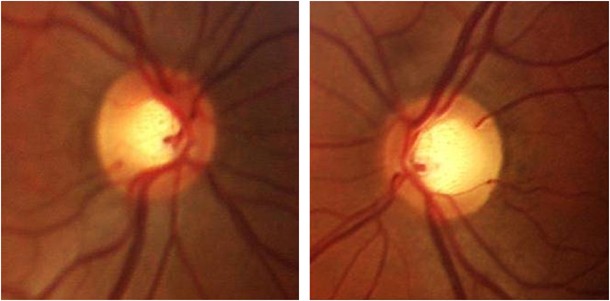

2. 두눈간의 유두함몰비가 0.2 이상 차이나는 경우(C/D ratio difference 0.2)

3. 0.6 이상의 유두함몰비 (C/D ratio > 0.6)